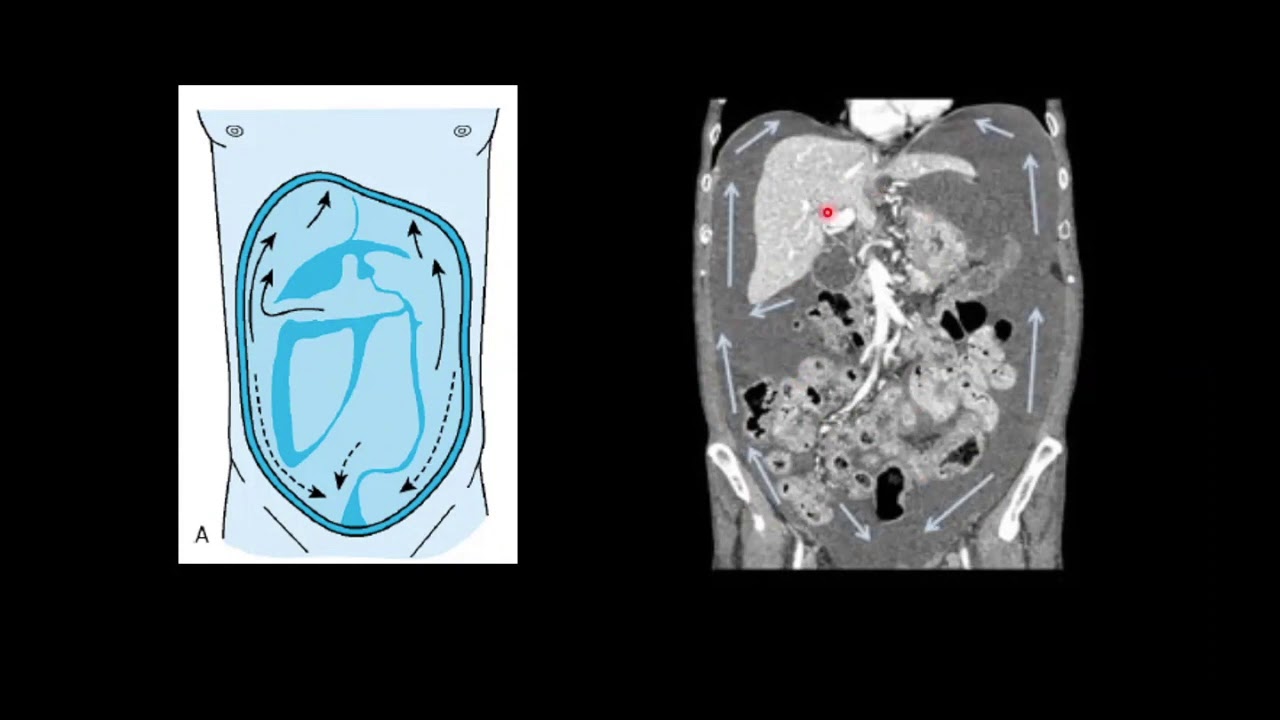

So, notice here that this part of the pleura of the peritoneum is sculpted, they surround this piece, so to speak, the entire abdominal wall from the inside, the entire abdominal wall, everything you see here in blue is the parietal peritoneum. While when this membrane, instead of covering the walls of the abdomen, when this membrane stops covering them and begins to lay on top and now cover the viscera of the organs that are contained within the abdomen, it becomes visceral peritoneum, But they are not two isolated entities, they are one on top of the other, notice that the visceral peritoneum, for example, here is surrounding the liver and then here it begins to surround the stomach, here, for example, it begins to surround the vessel, which is why the visceral peritoneum is the sheet or layer of the peritoneum that surrounds the viscera or the organs and is what will make them shiny, while the parietal peritoneum is what would then wrap or cover the walls, but notice here that for example this is still parietal but when it retracts it becomes visceral, then it is the same parietal that when it retracts over an organ it becomes visceral, then this visceral, see, goes all the way around, all the way around, all the way around and here it folds back in and becomes to become parietal it continues to be parietal, parietal again visceral, visceral, visceral turns everything around, it is like a chain, it is a continuity and then the visceral will become parietal again, if we see it here from the side For example, here we see in blue the entire parietal peritoneum surrounding the diaphragm in the muscles on the wall of the abdomen. Down here it has a limit surrounding the pelvic structures but above them, that is why the pelvic structures are not considered structures that are inside the peritoneum because they are excluded by it and then here again it begins to stick to the posterior abdominal wall, that is why that would be, the parietal peritoneum would be the blue one, Now when it folds back, for example, over the liver, the stomach, the transverse colon, these are the loops of the small intestine.

Let's talk then about the compartments of the large peritoneal cavity, which is what generally confuses students, look at all this that I 'm marking here in black is the parietal peritoneum, notice attached to the posterior abdominal wall, posterior wall, here at the diaphragm, the anterior abdominal wall, means that everything that is inside that parietal peritoneum is the so-called large peritonial cavity or they also call it the greater cavity or simply the large abdominal cavity but it turns out that within that abdominal cavity there is a smaller cavity that It would be the trans cavity or after cavity, excuse me. Here it is not trans with N, but after the omentum cavity, also called the bursa. omental or omental sac, this cavity is quite important, in fact it is a subdivision of the large abdominal cavity and that is why it is sometimes called even the minor peritoneal cavity, the large peritoneal cavity which is the green one is called the large cavity or the greater cavity, while it is behind the cavity of the omentums, they generally call it the lesser cavity or the small cavity, it is important to study it so much that I dedicate the third part of the peritoneum videos to it, in the first two videos we will talk about the great peritoneal cavity because you see that it is large, it deserves to talk about it, in the third video we will talk about it after the omentum cavity and finally there is a space that is behind that parietal peritoneum, that is, it is between the parietal peritoneum that is in the back part of the abdomen and then let's call it the musculature and the bone part of the back of the abdomen, so this space that is behind this parietal peritoneum that I am putting here in yellow is the famous retroperitoneum, the The same name tells you is the space that is behind the peritoneum, it is not considered part of the large abdominal cavity and there I dedicated a separate video to it, which is the retroperitoneum video that is also uploaded to the channel along with these, which have to See it in order peritoneum 1 2 3 and then retroperitoneum so that you can perfectly understand what retroperitoneum corresponds to.

For example, this is a cross section that we already saw right now, what you see in blue is the posterior parietal peritoneum, I tell you that because everything that is behind it that I am putting here in green is the famous retroperitoneum , which is a space virtual, this is really a virtual space where we find the pancreas, the kidneys, many viscera that we are going to see later in the retroperitoneum video, everything that is in front of that parietal peritoneum within the large abdominal cavity is the large peritoneal load and Remember that inside the large peritoneal cavity there is a smaller sub-cavity which is the after cavity of the omentums, which well you will understand later, here what I want you to know is: how they exist or what the compartments that form the peritoneum are like, these They are the big three. Let's stay with this image for example, this entire membrane that we see here as it is attached to the posterior abdominal wall, that is what you see there transparently in the background, that retroperitoneum in fact everything you see here in the background is the retroperitoneum: kidneys, pancreas, ureters second, third and fourth portion of the duodenum, the abdominal aorta, the inferior vena cava, all are considered retroperitoneal organs or viscera because they lie behind that parietal peritoneum. Seen here now, let's talk, let's stay with the large peritoneal cavity, which is what we will dedicate these first two videos to, this large peritoneal cavity is subdivided again, what structures subdivide them?